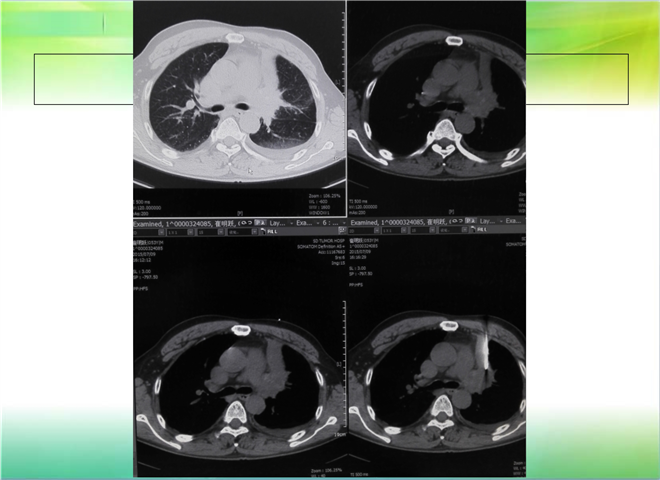

CT引导下穿刺活检术